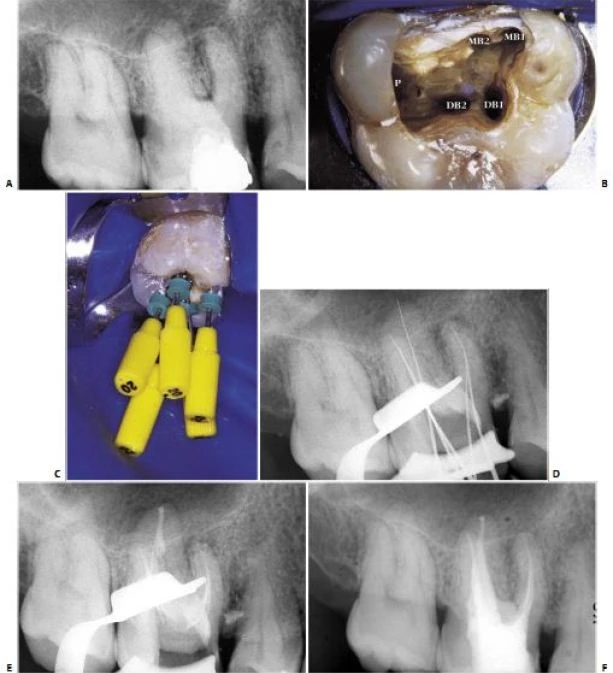

Về mặt giải phẫu học, răng cối nhỏ thứ nhất trên có thể có hình dạng hoàn toàn khác. Ống tủy cong hình lưỡi lê ở 1/3 chóp chân răng là một dạng điển hình. Hiếm khi tìm thấy một ống tủy đơn, hình elip trong một chân răng; thường gặp hai ống tủy giao nhau ở 1/3 giữa với hai lỗ chóp trong một chân răng (38%) hoặc hai ống tủy (thường cùng chiều dài) ở trong hai chân răng riêng biệt (60%). Hiếm hơn nữa có thể thấy ba chân răng với ba ống tủy và những lỗ chóp riêng biệt, chiếm 6% theo Carns và Skidmore , và 5% theo những tác giả khác. Trong những trường hợp này, RCN có hình dạng như răng cối lớn. Một ống tủy rộng hơn ở phía trong và hai ống nhỏ hơn ở phía ngoài, một ở phía gần và một ở phía xa (hình 11.46). Điều trị nội nha tốt hay không phụ thuộc vào việc tạo xoang tủy có đúng hay không: răng cối nhỏ trên với ba ống tủy thì cần tạo một xoang tủy có hình dạng chữ “T” với sự mở rộng theo chiều gần xa ở phần ngoài của xoang truyền thống. Sự thay đổi này cho phép tạo một đường vào tốt cho cả hai ống tủy ngoài. Nếu ba chân răng phân kỳ, ta có thể thấy được trên phim X-quang trước điều trị. Nếu ba chân răng chụm hoặc chồng lên nhau (hình 11.47A), ta có thể biết được trong lúc điều trị. Nha sĩ có thể nghi ngờ có hai ống tủy ngoài không chỉ nhờ vào sự hiện diện của 2 miệng ống tủy (thường không nhận ra hai miệng ống tủy riêng biệt), mà còn nhờ vào hướng của cây trâm thăm dò khi nó đi vào một trong hai ống tủy, hoặc hình dung trên phim X-quang thấy hình ảnh dị dạng nhưng những đường nét chung của chân răng vẫn bình thường [ví dụ: hoàn toàn nằm về phía gần (hình11.47 B)], ta có thể nghi ngờ còn một ống tủy ngoài thứ hai nữa mà hướng của nó nằm về phía xa hơn so với ống thứ nhất (hình 11.47 C, D).

Hình 11.47. A. Phim trước điều trị răng #14: Chân răng chồng lên nhau, không dễ nhận ra ba ống tủy. B. Dụng cụ đầu tiên được đừa vào miệng ống tủy (dường như là ống ngoài), hình ảnh dụng cụ đi theo một hướng bất thường so với hình ảnh chân răng. Nhìn kỹ thấy nó chuyển hướng về phía gần: dụng cụ đã đi vào ống gần ngoài. C. Uốn cong dụng cụ về phía xa rồi đưa vào cùng miệng ống tủy này, nó tự động đi vào ống xa ngoài. D. 34 tháng sau, phim X-quang cho thấy sự hiện diện của ba ống tủy.